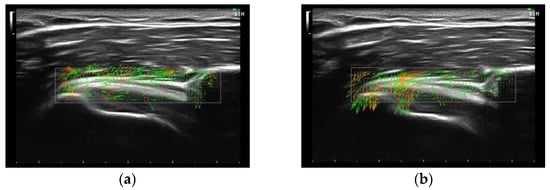

2.2. Experimental Data Acquisition and Analysis